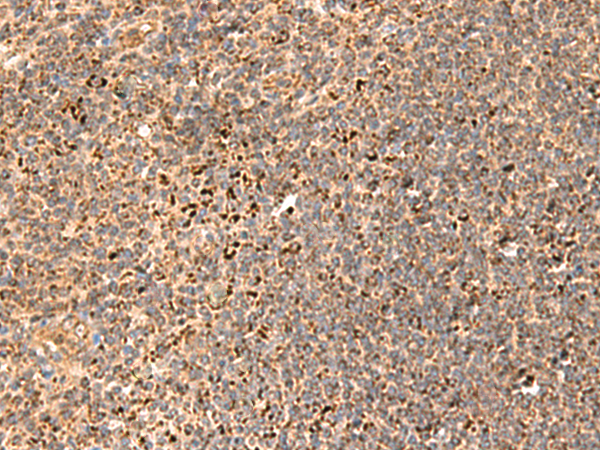

分类: 科研抗体货号: P10105别名: REGH; REGL; PSPS2; REGI-BETA应用: WB,IHC反应种属: Human